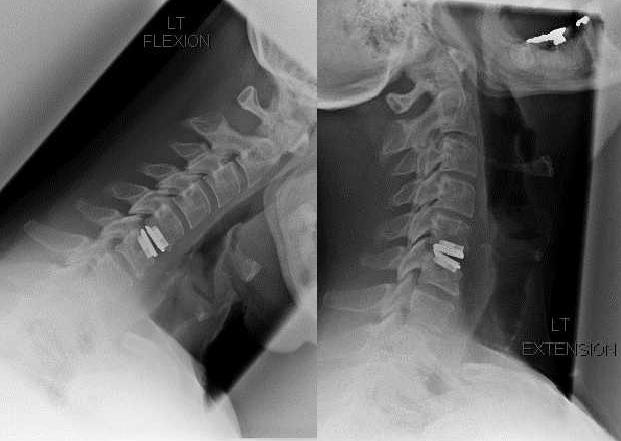

| Рентгенография | На полученных снимках визуализируется уменьшение расстояния между телами позвонков, разросшиеся края костных пластинок. Исследование информативно для выявления врожденных или приобретенных аномалий позвоночника, предшествующих травм |

| МРТ, реже — КТ | Позволяет обнаружить не только место выпячивания, но и его размеры, вид, форму, степень сдавления расположенных рядом соединительнотканных структур |